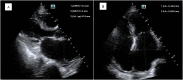

La pillola di dicembre, mostra la gestione del paziente già citato nell’argomento del mese. Riassumendo: paziente con via aerea difficile, intervento di stabilizzazione toraco-lombare, rinviato per intubazione fallita, con arresto…